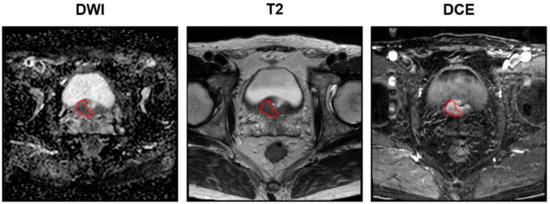

For each patient, tumor delineation was performed by manually placing the ROI on T2WI, ADC map, and DCE images, according to the histopathological results (Figure 2). Tumor ROI was depicted for each patient’s index lesion using a three-dimensional (3-D) slicer. The lesion with the largest diameter or that demonstrating ECE was considered the index lesion. Tumor ROI measurement encompassed the maximum possible lesion extent in the image with the greatest visibility.

Figure 2. Examples of delineation on mpMRIs: DWI (left), T2 (middle), and DCE (right) sequences. The red circles denote the tumor ROIs. Images acquired on a Philips 3T Scanner. Scan magnification scale: ×1. The patient’s information: post-RP BCR (+), initial PSA of 13.32 mg/dL, mpMRI: suspicious ECE (cT3a), surgical pathology findings: GS of 9 (4 + 5), ECE (pT3a), no lymph node involvement (pN0), PSM. mpMRI = multiparametric magnetic resonance imaging; DWI = diffusion-weighted image; T = Tesla; DCE = dynamic contrast-enhanced; RP = radical prostatectomy; BCR = biochemical recurrence; PCa = prostate cancer; GS = Gleason score; ECE = extracapsular extension; PSM = positive surgical margin.